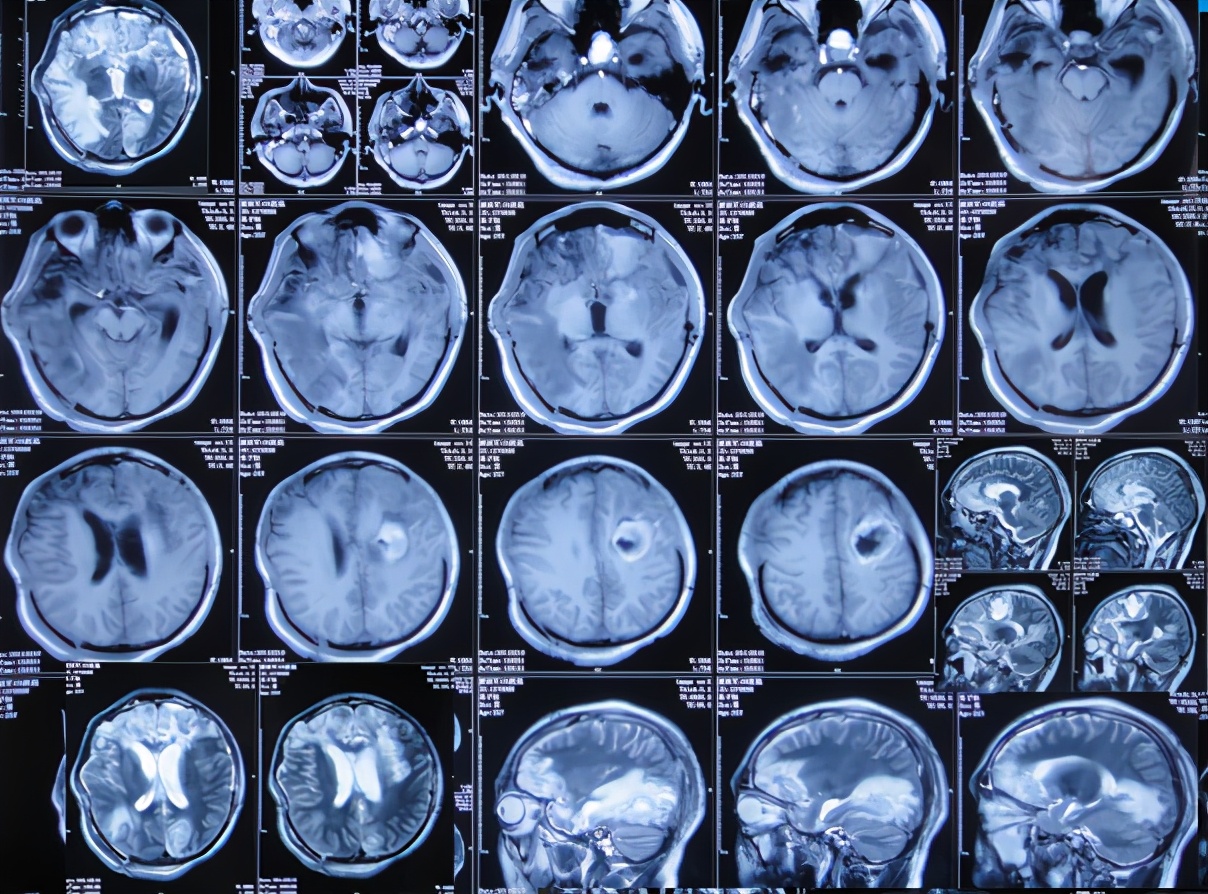

术后患者生命渐趋稳定;但开颅术后26天即2011年2月10日,复查头颅MRI:轻度脑膨出,脑水肿( 图-3 )。

图-3: 2011年2月10日头颅MRI

在第2家医院治疗45天时即2011年4月6日即开颅术后81天,仍能简单的遵嘱活动,能简单言语,如“爸爸、妈妈”;查头颅CT示:颅骨缺损,仍脑水肿,且出现脑室扩张( 图-4 );但没有给予处理。

图-4: 2011年4月6日头颅CT